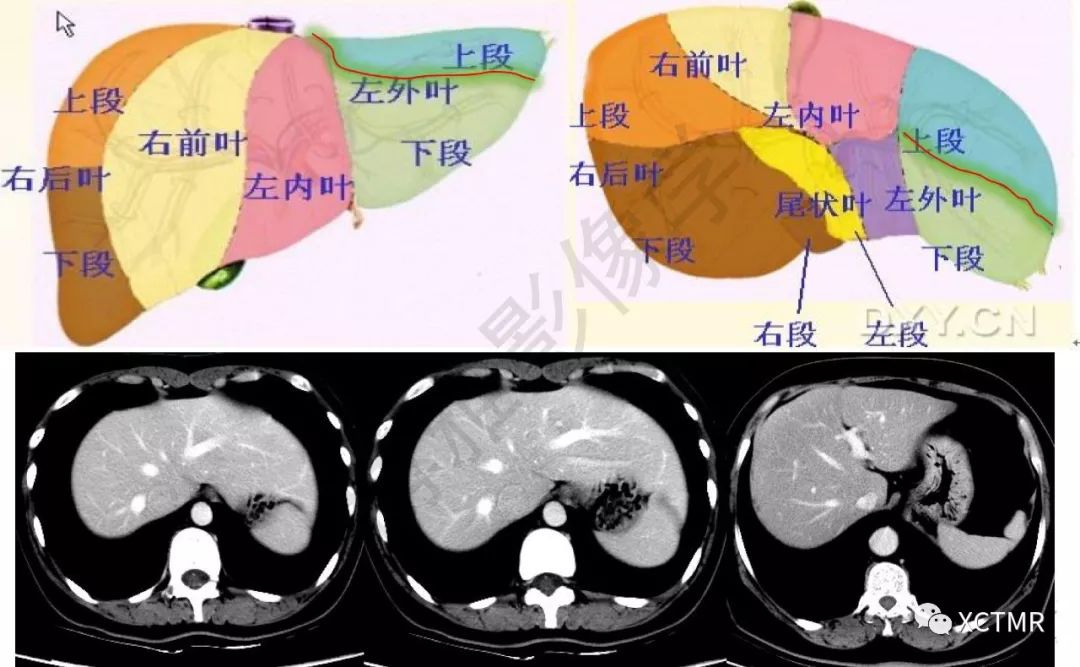

肝couinaud分段的ct影像学

肝脏分叶分段的影像学解剖

外叶下段,s4为左内叶,s5为右前叶下段,s6为右后叶下段,s7为右后叶上段

上腹部ct断层肝脏解剖及肝段分布腹部淋巴结分布